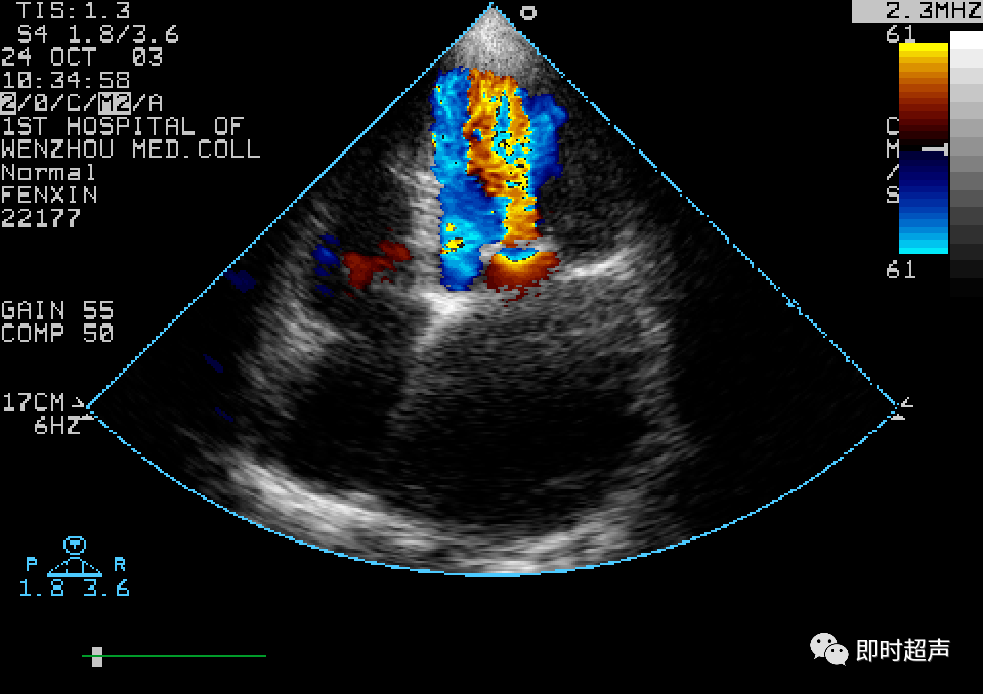

左心室舒张末内径lvdd 52mm,左心房内径lad 57mm,pasp 63mmhg,二尖瓣

心脏瓣膜病超声诊断_二尖瓣